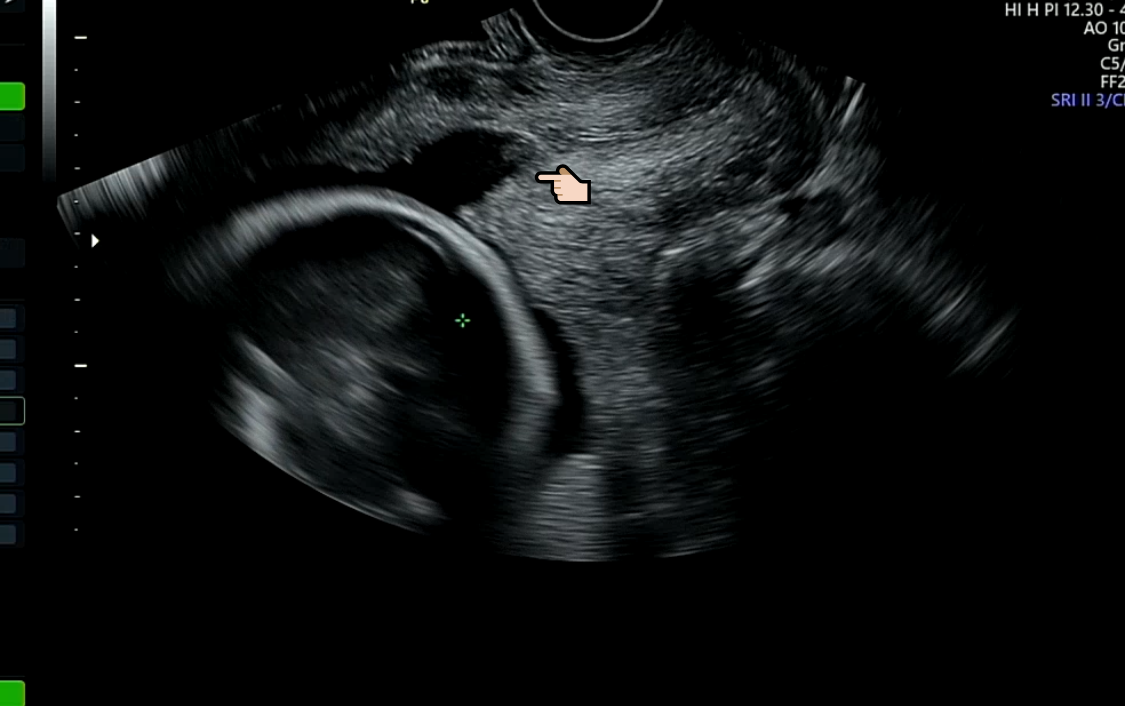

그리고 초음파를 살펴보니 아기 머리가 있는 경부쪽이 살짝 열렸다고 했다..(헐)

그건 열리기도 하고 닫히기도 한다고.

가자마자 수축검사하고, 초음파보고..